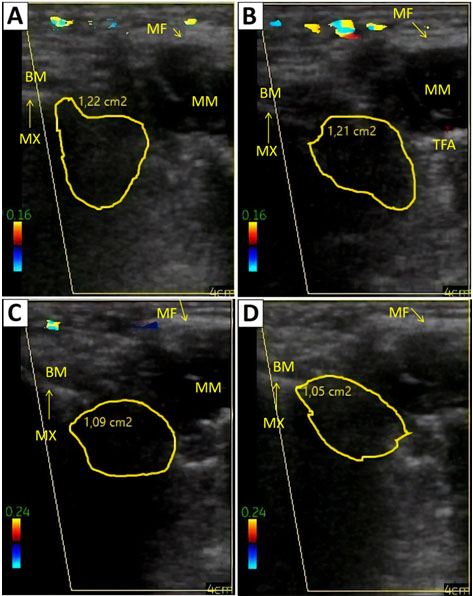

The submalar region was then immediately checked with US for the assessment of the tissue condition and the remaining volume. The examination confirmed the buccal extension removal, as it can be seen through the comparison between the pre-bichectomy (Figure 1C, Figure 1D) and the post-bichectomy echographic images (Figure 2A, Figure 2B).

One hundred and eight days after the procedure, US was performed once again by the same radiologist and the clinical success of the procedure was determined (Figure 2C, Figure 2D). The patient also stated that she was very satisfied with the outcome.

Figure 2: Ultrasonographic images of the buccal fat pad after surgery. (A, B) Images taken immediately after the bichectomy, showing the region in transverse and longitudinal positions, respectively. (C, D) Images taken 108 days after the bichectomy. BM: Buccinator muscle (hypoechoic); MM: Masseter muscle (hypoechoic); TFA: Transverse facial artery; MF: Masseteric fascia (hyperechoic); MX: Maxilla (hyperechoic).